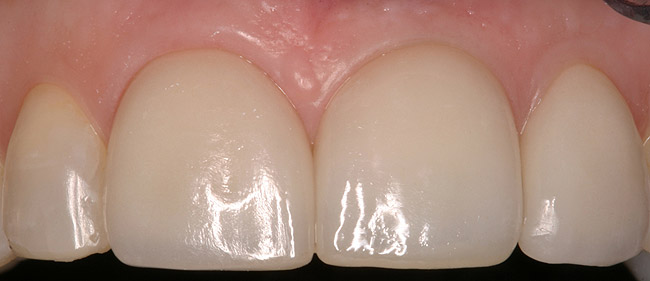

Figure 5a  Congenitally missing lateral incisors. Postorthodontic therapy, prior to implant placement.

Figure 5a

Figure 5b  Congenitally missing lateral incisors. Postorthodontic therapy, prior to implant placement.

Figure 5d  Completed, porcelain-fused-to-gold implant restorations, custom gold abutments, lingual-set screw-retention, Kerr Extrude¬Æ light-body crown-abutment seal.

Figure 5d

Figure 5e  Completed, porcelain-fused-to-gold implant restorations, custom gold abutments, lingual-set screw-retention, Kerr Extrude¬Æ light-body crown-abutment seal.

Figure 5e

Figure 5f  Completed, porcelain-fused-to-gold implant restorations, custom gold abutments, lingual-set screw-retention, Kerr Extrude¬Æ light-body crown-abutment seal.

Figure 5f

Figure 5g  Completed, porcelain-fused-to-gold implant restorations, custom gold abutments, lingual-set screw-retention, Kerr Extrude¬Æ light-body crown-abutment seal.

Figure 5g

Of all the options presented, when treatment planned and performed to recommended implant surgical and prosthetic guidelines, this option is the most conservative from biological standpoint. The esthetic outcome can be as natural as the tooth it is otherwise replacing (Figure 5).13-15 Patient satisfaction for such successful treatment outcomes is high.16 However, not all patients who are missing a single anterior tooth are ideal candidates for implant therapy. There may be medical contraindications, significant site preparation required, and/or financial constraints. Dental providers may find the resin-bonded or conventional FPD option a more suitable treatment modality with the patient accepting the associated disadvantages and limitations. If this is the case, it is important to have a wider overall treatment outcome picture when comparing the different options.17 From a long-term perspective, few patients perceive real value to either doing nothing or choosing an RPD. Consequently, this leaves the two main contenders: conventional FPD therapy versus single-tooth implant therapy.